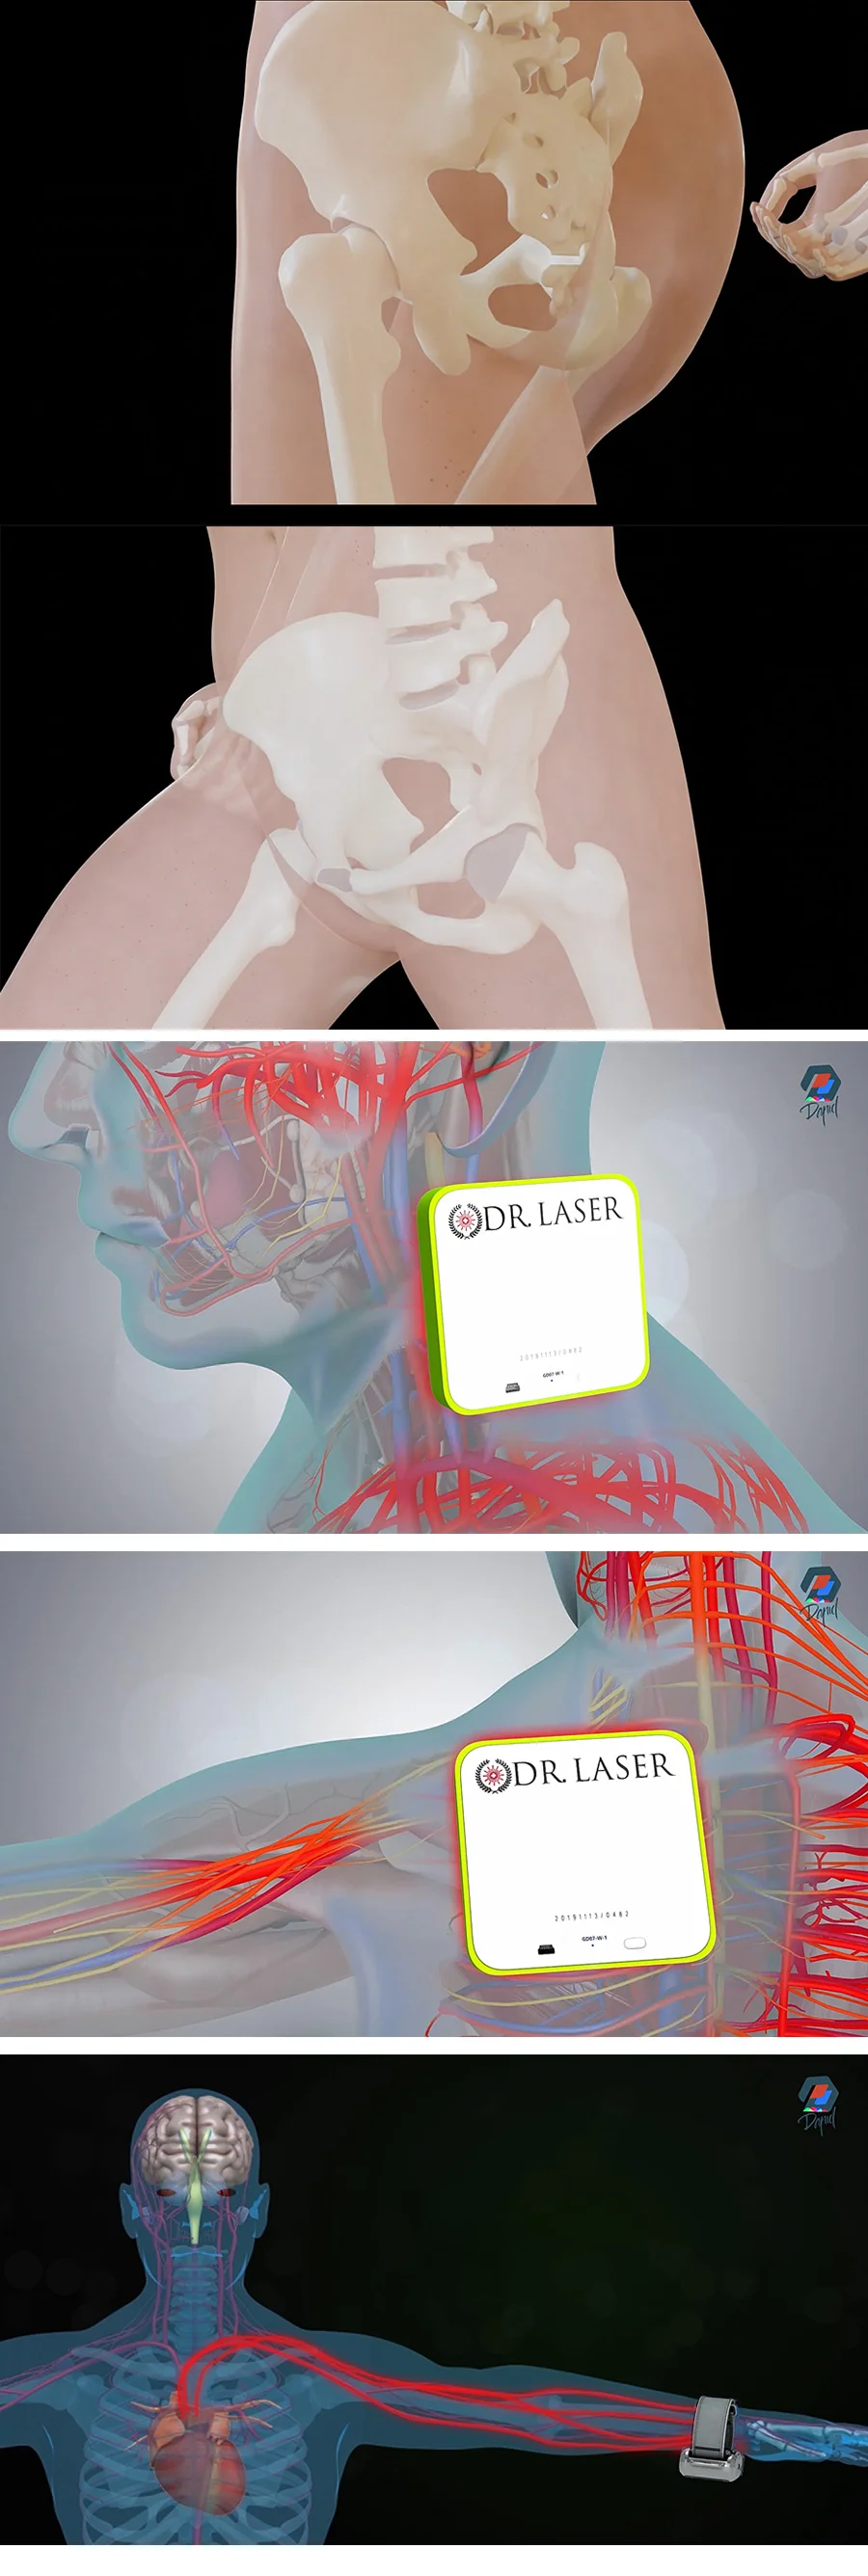

의학 관련 : 의료 효과,신체 해부학

의료, 의학 , 의료기기 시뮬레이션 제작

ex) 피부에 화장품이 스며드는 장면 ( 세포, 입자 등)

ex) 신체조직 혹은 신체안에서 변화&반응하는 시뮬레이션

ex) 의료기기의 원리